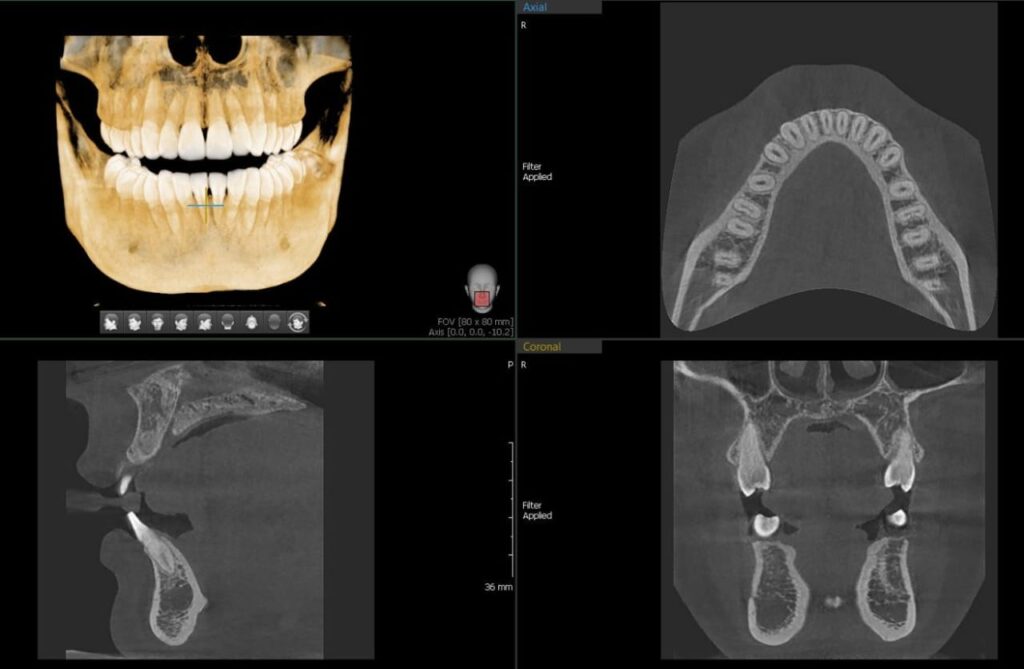

3D CBCT is done when detailed three-dimensional imaging of the jaws and teeth is needed. Key uses include:

- Accurate planning for dental implants: bone volume, nerve position

- Assessment of impacted teeth, orthodontic treatment and jaw-bone structure

- Locating root-canal anatomy, hidden pathology, cysts/tumours in the jaw

Because our Vatech system captures full volumetric scans, clinicians can visualise anatomy in all planes and plan with precision.

- The system includes advanced artifact-reduction technology, reducing the impact of metal restorations so images remain sharp and diagnostically useful.

- It offers canal-drawing visualisation in 3D, allowing precise tracing of root-canals and nerves for endodontic and implant planning.

- You will receive a high-resolution 3D dataset, enabling your clinician to visualise anatomy from all angles with confidence.